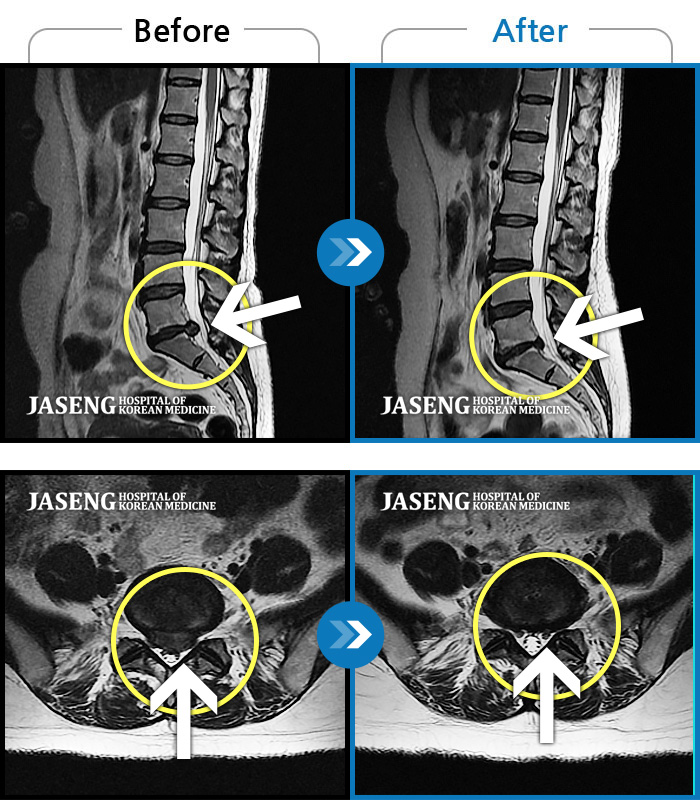

No.55 조회수 91 2022.07.08

No.54 조회수 380 2021.12.17